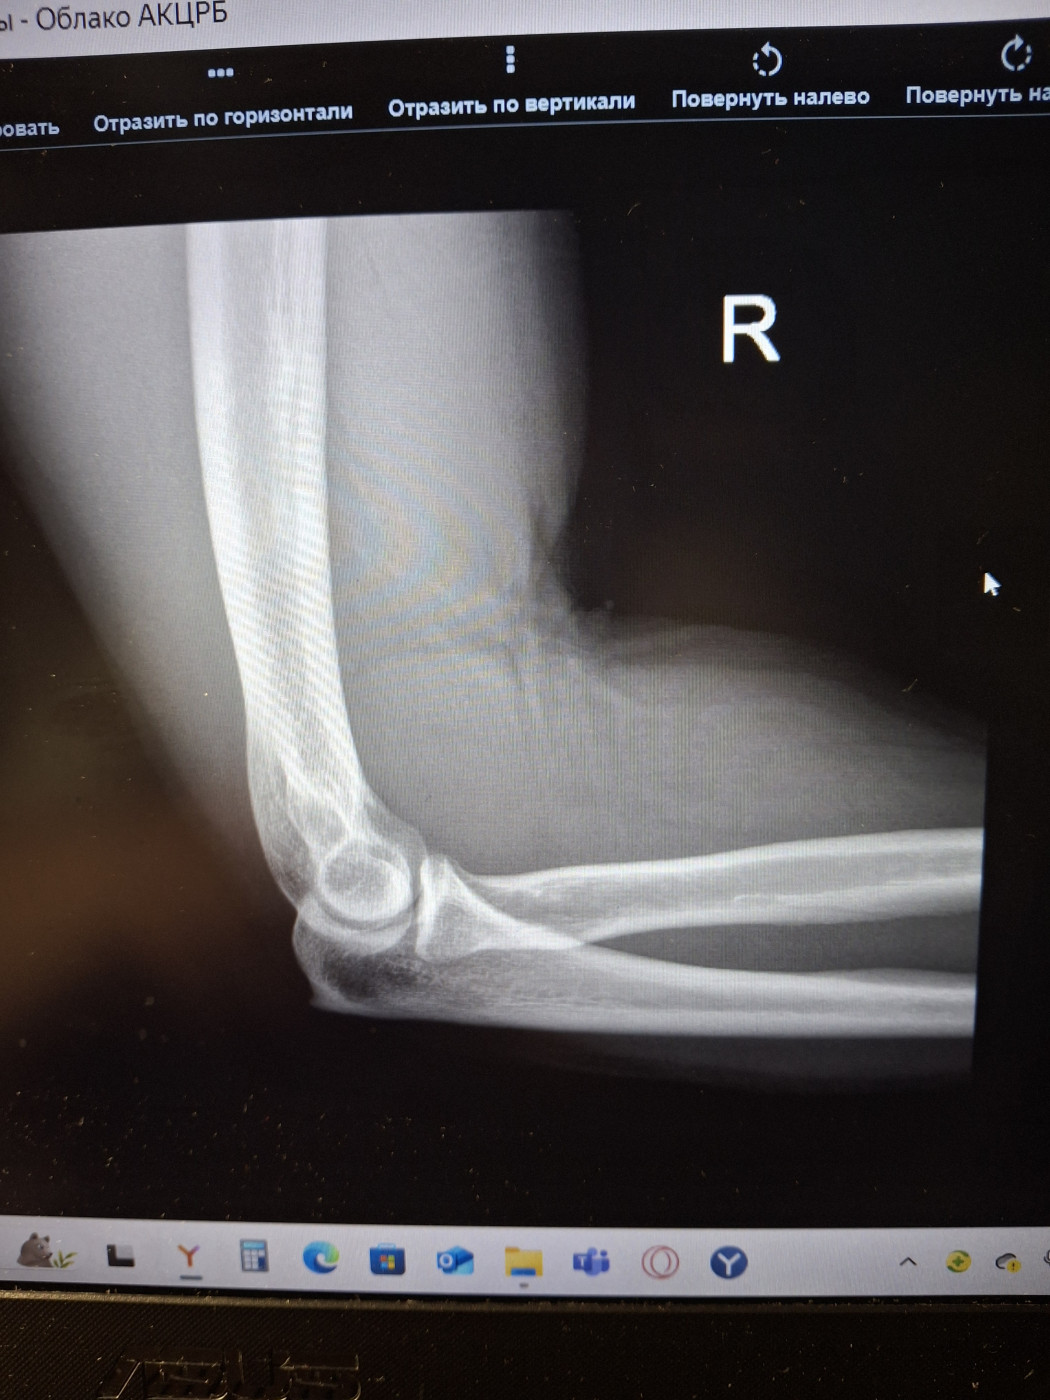

Боль в коленом суставе